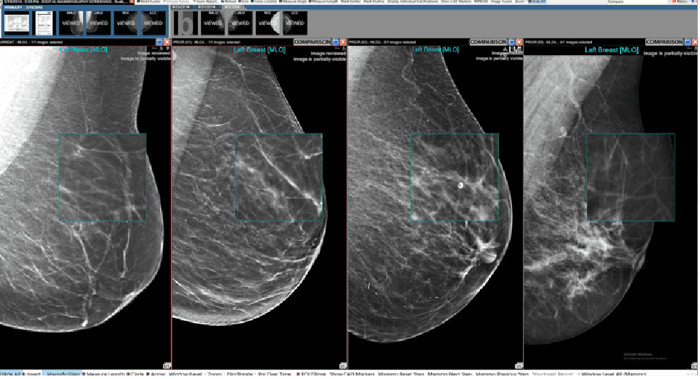

Integrated mammography viewer that enables you to ergonomically read a wide variety of breast imaging studies as well as studies from all other specialties all in one place. NovaMG Pro can be a stand alone solution that works with any PACS or be added to Novarad's enterprise imaging software.

2D and 3D breast Imaging

Essential for providing detailed, multi-dimensional views that are crucial for the early detection and accurate diagnosis of breast conditions.